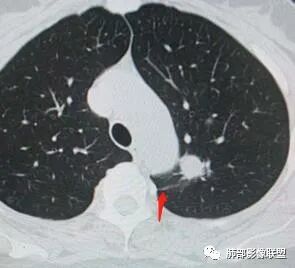

二、看第二个结节

1、密度?

2、边界?

3、收缩力?

4、血管?

5、大小、内部结构、CT值

金豆

纯磨玻璃 边界清

小兜

磨玻璃,边界清

三个石头

纯磨玻璃,能画出轮廓,但是感觉边缘又比较模糊,是层厚原因吗,收缩力弱,血管进入

心灵鸡汤

与左肺上叶纵隔旁pGGN

南边

三、看看这一个

1、密度:PGGN?MGGN?

lmg

这个密度要高一些,混合磨玻璃结节

MGGN,比上面两个密度高

这个结节中间密度稍高一些 不像纯的

都认为mggn,都觉得密度高了?

三.右肺上叶胸膜下结节及左肺上叶血管旁结节,尽管都是磨玻璃密度,但都比较小且边缘特征不明显,恶性征象未显露,处置并无特殊,定期复查!